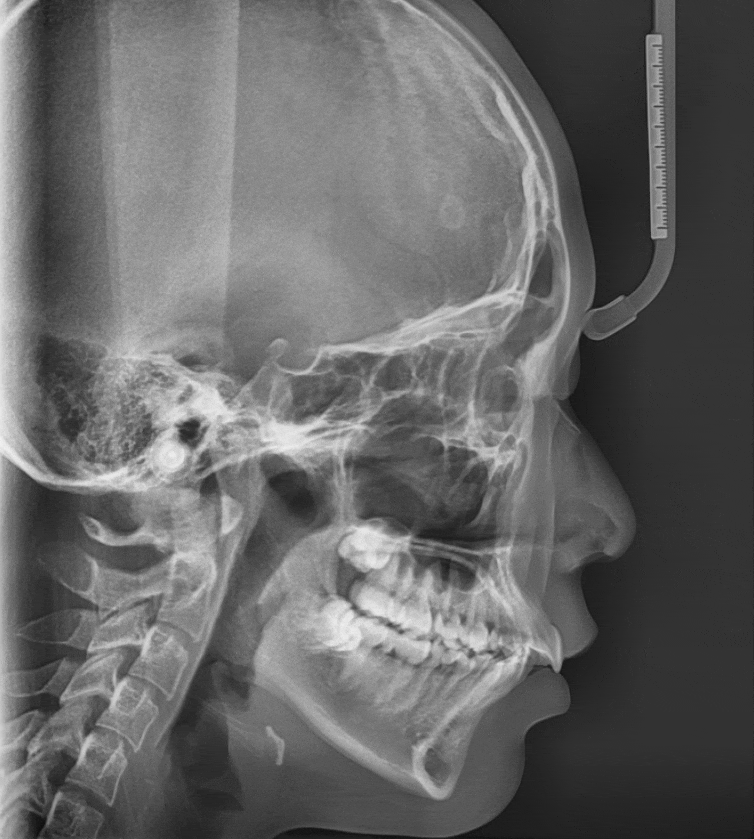

241122 치아를 움직이는데 이렇게 과학적이랍니다~~~